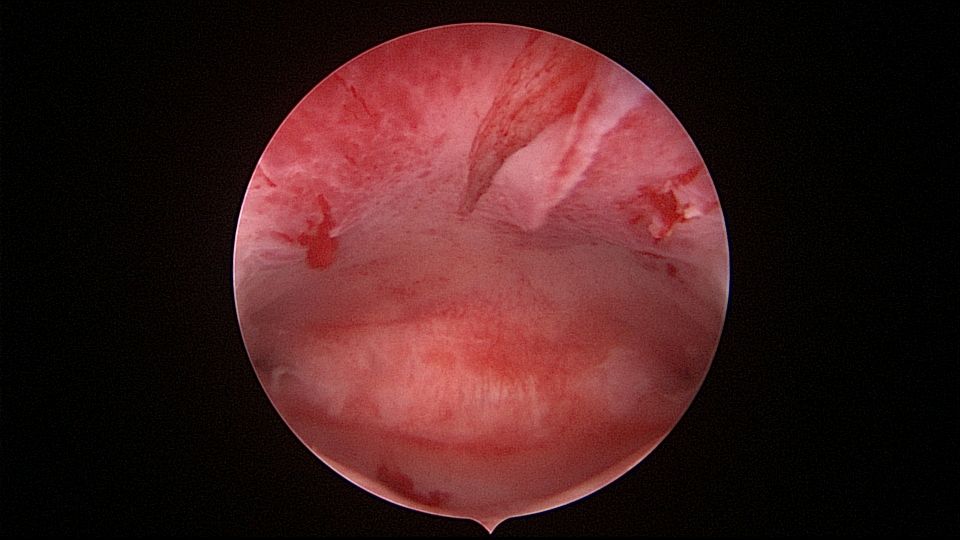

患者29岁,G1P0,继发不孕,2020年8月宫腹腔镜探查,大网膜与腹前壁多处粘连,子宫后壁与直肠前壁广泛粘连,宫腔中央型宽大柱状粘连,宫腔两侧少许粘连。电钩分离盆腔粘连,冷刀分离宫腔粘连,恢复宫腔形态,显露双侧输卵管开口,术中美兰通夜,双侧输卵管通畅。2020年10月宫腔镜二探取球囊,宫腔形态正常,双侧输卵管开口可见。2021年3月自然妊娠,外院足月分娩。现34岁,G2P1。